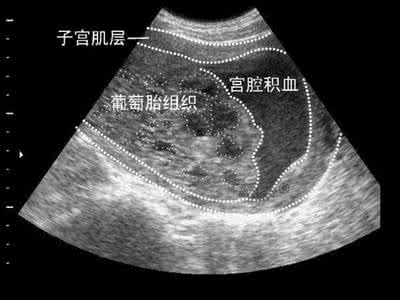

葡萄胎其实是异常受精后无法正常发育成胚胎的病变,是因妊娠后胎盘滋养细胞异常增生,间质水肿,终末绒毛转变成大小不一的水泡,相互连接成串,状如葡萄而得名。又被称为“水泡样胎块”,我国很常见。那么,葡萄胎是什么呢?

葡萄胎分为完全性葡萄胎和部分性葡萄胎,完全性葡萄胎占多数。一般发生于生育期任何年龄,以20-30岁和40岁副绝经前这两个年龄组发病较多。大于40岁及小于20岁是发生完全性葡萄胎的高危因素,部分性葡萄胎与孕妇年龄无关。葡萄胎多被认为是滋养层发育异常,其病理特点和生物学行为不同于其他肿瘤。

完全性葡萄胎与部分性葡萄胎相比,部分性葡萄胎的恶变可能性比较少,一般葡萄胎仅限于宫腔内,这称为良性葡萄胎;也有一部分葡萄胎侵入子宫肌层,甚至发生更远处的转移,这称为有恶变行为的侵蚀性葡萄胎。对于葡萄胎出现以下两种情况需要化疗:一种是有高危因素(如有恶变行为的),另一种是清宫后,随访困难的(如家住山区,交通不便)要化疗。特别指出,清宫后定期到医院复查很重要。如有恶变行为,要及时进行化疗。而且在1~2年内,要做好避孕措施。